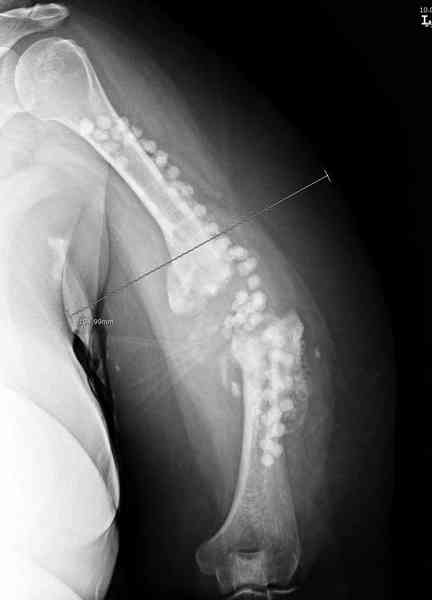

Хотя сам не стороннник применения более массивных

имплантов для плеча, но для этого случая сделали

исключение. На снимке 4А диаметр мягких ткани около 20 см, при весе больной более 135 кг, и также выступление Андрея Волны подстегнуло к применению более массивной 4.5 мм локинг пластины.